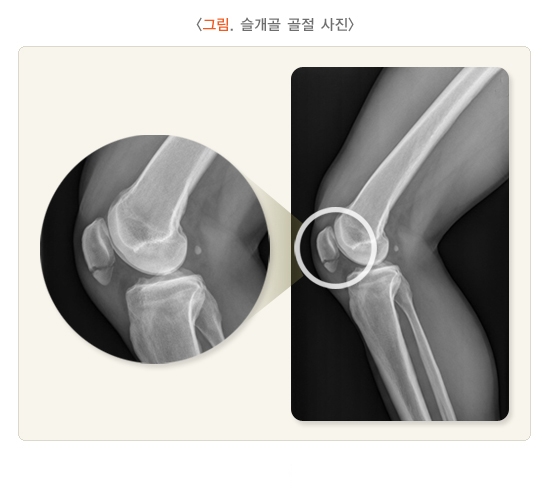

무릎은 우리 몸에서 가장 크고 복잡한 관절로, 걷기, 앉기, 계단 오르기 등 대부분의 일상 동작에 관여합니다. 따라서 무릎에 골절이 생기면 단순히 뼈가 붙는 것 이상의 회복이 필요하며, 관절 기능의 정상화를 목표로 해야 합니다.

무릎 골절은 특히 고령자에게서 자주 발생하며, 낙상 사고나 교통사고, 스포츠 손상 등 다양한 원인으로 나타날 수 있습니다. 수술 후에는 일상생활로의 복귀를 위한 재활 과정이 매우 중요합니다. 이 글에서는 무릎 골절 수술 후 회복 기간과 빠르게 회복하기 위한 팁을 체계적으로 소개합니다.